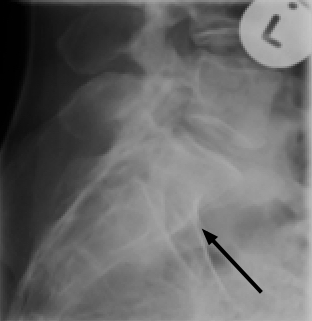

An lateral xray of the lower back reveals an unusual alteration in the normal lordosis at the thoraco lumbar junction; nothing specific but confirming her extreme sensitivity in the region.

A closer look at the spot of L5/S1 reveals the presence of a large spatulated transverse process of L5 on your reading left (black arrow), together with a sagittal facet (red arrow); on the right is the conventional coronal facet.

Again, on the lateral spot, there is the suggestion of incomplete union between S1 and the remainder of the sacrum; fortunately the disc space at L5-S1 is normal. Or, using other conventions, the partially fused segment is in reality L5, making this a sacralisation.

The irritation of the sciatic nerve is almost certainly not for a bulging disc, but that could only be confirmed by MRI scan. Rather, this is the release of noxious chemicals from the joint cartilage.

Rudimentary ribs are seen at T12, a common feature of a sacralisation or lumbarisation. Naming is not important; whether the last discrete vertebra is L4 or 5 makes no difference. What is significant is the presence of a transitional segment, asymmetrical facets, a transverse ilio anomalous joint and those little appendages arrowed at the thoraco lumbar junction.

These anomalies sometimes produce quite unusual and even bizarre patterns of lower and upper lumbar pain with diverse thigh and calf radiation.